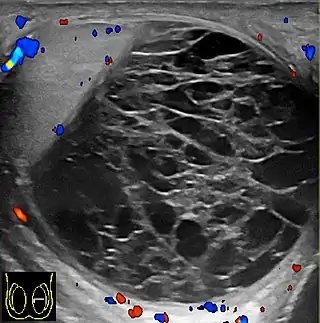

![]() Ecografía escrotal de un hematocele, un par de semanas después de su aparición, como un volumen líquido con múltiples tabiques gruesos. El hematocele no muestra flujo sanguíneo en la ecografía Doppler. Un piocele tiene una apariencia similar, pero fue descartado por falta de inflamación. | ||